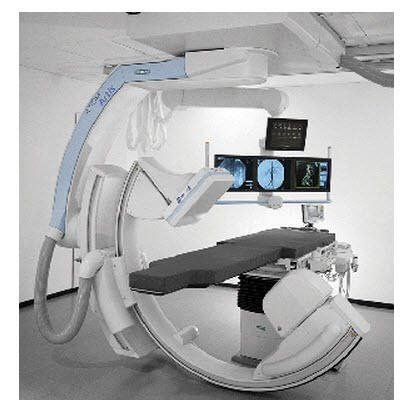

血管造影机(DSA)

项目类型

器械质押区

起投金额

1800USDT

每日释放:0.7

释放周期:50 天

已购: 20000

剩余: 0